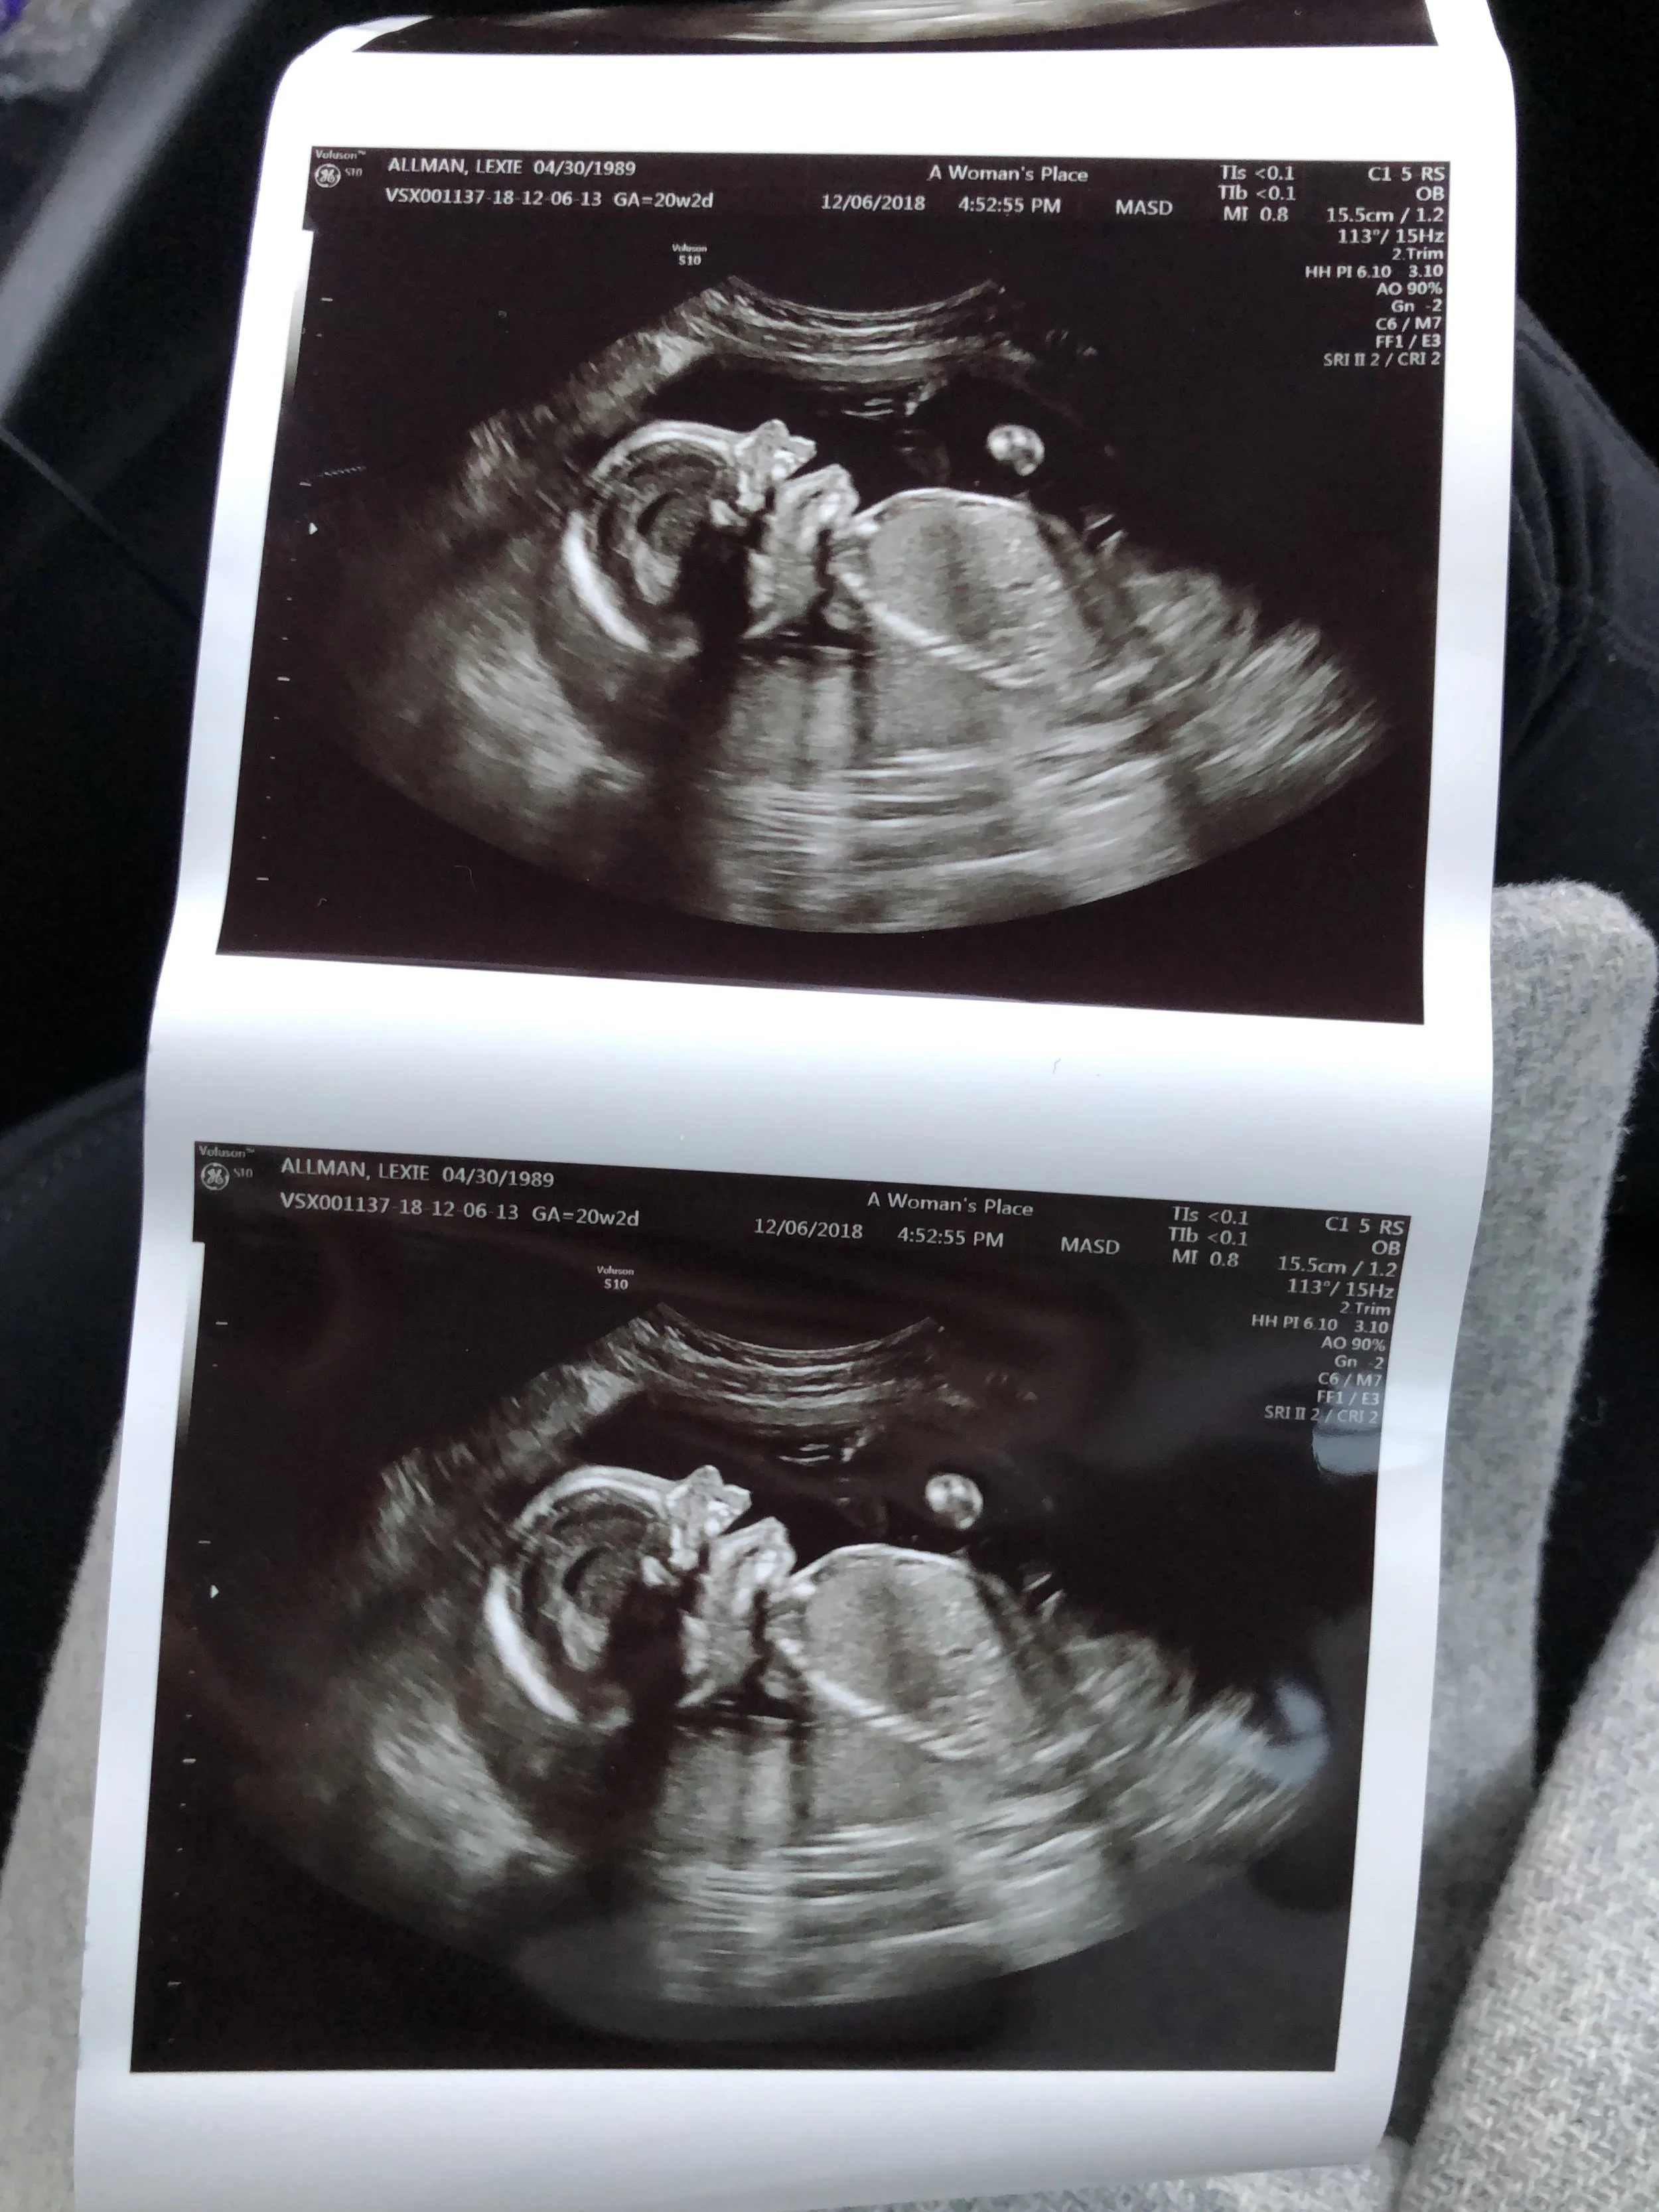

Pregnancy Update Second Trimester Recap Lexsentials